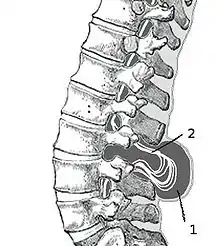

Spina bifida occulta

Часто эта форма называется «скрытое расщепление позвоночника», так как при этом спинной мозг и нервные корешки в норме, а также отсутствует дефект в области спины. Данная форма характеризуется лишь небольшим дефектом или щелью в позвонках, которые формируют позвоночный столб. Зачастую эта форма патологии настолько умеренно выражена, что не вызывает каких-либо беспокойств. При этом такие больные даже не знают о наличии у себя этого порока развития и узнают об этом лишь после рентгенографии. Чаще всего эта форма патологии возникает в пояснично-крестцовом отделе позвоночника. У 1 из 1000 больных могут отмечаться проблемы с функцией мочевого пузыря или кишечника, боли в спине, слабость мышц ног и сколиоз.